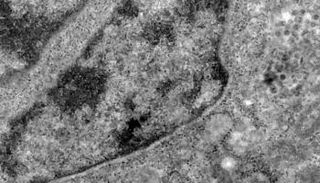

دراسة علمية تكشف حقيقة نشأة كورونا في ووهان الصينية

النوع (A) من فيروس كورونا نشأ في ووهان الصينية ويضرب أمريكا وأستراليا، و(B) يتوغل في بريطانيا، أما (C) فانتشر في أوروبا عبر سنغافورة

الباحثون حللوا بيانات 160 مجموعة من جينات كورونا المستجد تم جمعها من شتى أنحاء العالم، خلال الفترة من 24 ديسمبر 2019 حتى 4 مارس 2020.